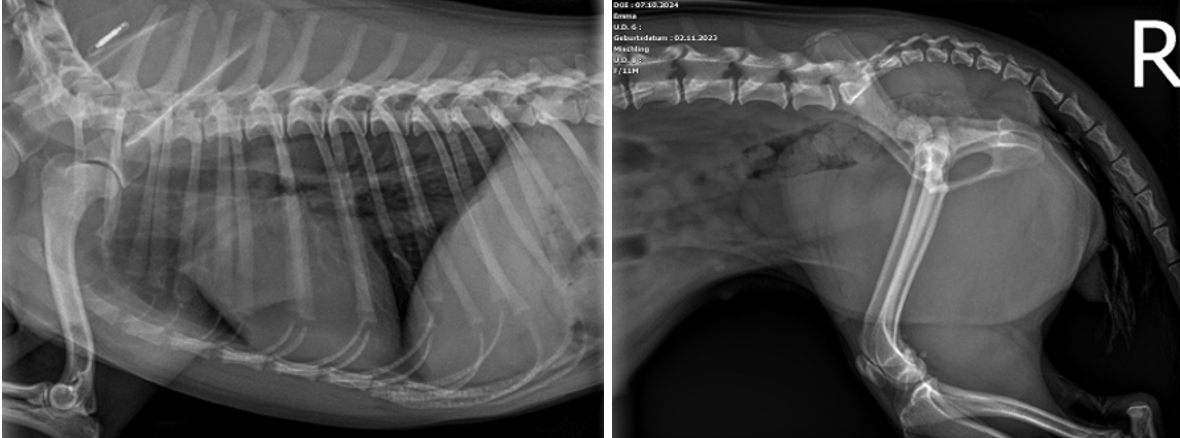

Auf der lateralen und ventrodorsalen Aufnahme des Beckens ist eine segmentale Fraktur des rechten Os pubis erkennbar. Es sind drei Frakturstellen identifizierbar (blaue Pfeile), eine zwischen Corpus ossis pubis und Ramus cranialis, die möglicherweise unvollständig ist. Eine weitere Fraktur im Ramus cranialis ossis pubis und die letzte zwischen Ramus cranialis und Ramus caudalis ossis pubis. Aus dieser Fraktur entstehen zwei Fragmente, von denen eines nahe dem Corpus ossis pubis liegt und geringgradig nach kranial verschoben ist, während das andere frei in den Weichteilen liegt und zwischen den beiden Frakturen zentriert ist. Die Konturen der Frakturen sind alle scharf abgegrenzt, was auf ein akutes Trauma hinweist. Die Symphisis pubis scheint leicht nach links lateral verschoben zu sein. Um eine Verschiebung des Beckens zu ermöglichen, sind drei orthogonale Frakturen erforderlich, die auf diesen Röntgenbildern nicht erkennbar sind.

Der rechte Femurkopf ist vollständig aus dem Acetabulum luxiert und nach kranial und dorsal verschoben (blaue Kreise). Die Weichteile des linken Femurs sind geringgradig verdickt. Im linken lateralen Aspekt der abdominalen Wand ist eine minimale Luftansammlung erkennbar. Beidseits sind die Coxofemoralgelenke geringgradig nach außen rotiert, welches eine laterale Positionierung der Patellae verursacht. Im rechten Kniegelenk befindet sich die Patella jedoch in medialer Position (blauer Pfeilkopf). Es ist unklar, ob ob diese traumatisch oder rasse-bedingt entstanden ist und welcher Grad der Patellaluxation vorliegt. Die sichtbaren caudalen abdominalen Organe sind ohne besonderen Befund.

Es handelt sich um eine akute, geschlossene, monostotische, segmentale Fraktur des rechten Os pubis, eine kraniodorsale Luxation des linken Femurs, eine mediale Luxation der rechten Patella und eine geringgradige Weichteilschwellung des linken Oberschenkels.